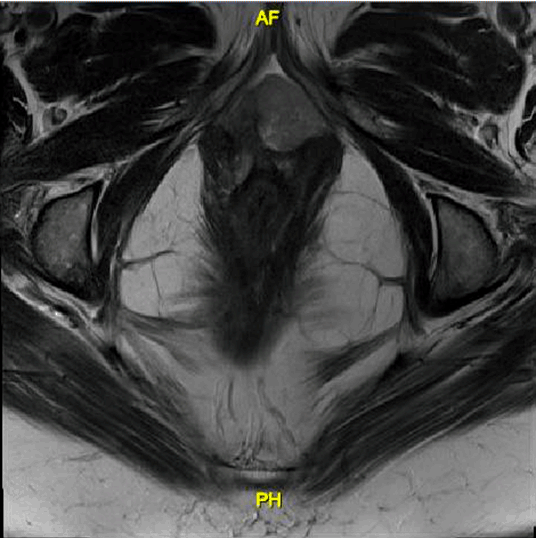

Since these images showed no evidence of metastatic disease, malignancy was presumed to be of primary vaginal origin. The patient underwent a bilateral inguinofemoral lymphadenectomy and bilateral pelvic lymphadenectomy with negative nodes followed immediately by a total pelvic exenteration to ensure negative surgical margins with resection of pubic bone, colostomy and diverting ileal urinary conduit. Intraoperative findings were significant for 4–5 cm exophytic anterior vaginal mass located 1 cm left of the urethra (Figure 2). Frozen section of the resected bilateral inguinofemoral and pelvic lymph nodes were negative for malignancy.

Figure 2: A 4–5 cm exophytic vaginal mass on gross specimen after removal.